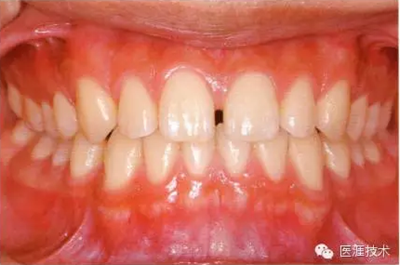

健康且正常的牙周組織臨床圖像

50歲女性的健康口腔內(nèi)部

圖為50歲女性,無特殊全身疾病,不抽煙。持續(xù)保養(yǎng)6年。無填充物等問題,依照患者本人要求持續(xù)觀察。牙周組織臉頰側(cè)雖見部分萎縮,但X線牙片顯示牙間無骨吸收現(xiàn)象,保持著比較健康的狀態(tài)。